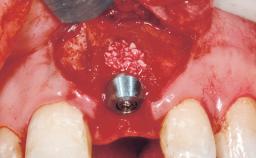

Late Placement of an Implant in a Maxillary Left Central Incisor Site

A 36-year-old female patient was referred for the replacement of the upper left central incisor (tooth 21), which had fractured. Although the tooth had been asymptomatic for many years, the crown began to loosen, at which time she presented to her dentist for an assessment. Teeth 21 and 22 had both been endodontically treated many years previously. She was a healthy individual and a non-smoker.

# of Implants 1

Type of Implants Two-Piece

Placement Protocol Early or late implant placement

Bone Volume Deficient horizontally, requiring prior grafting